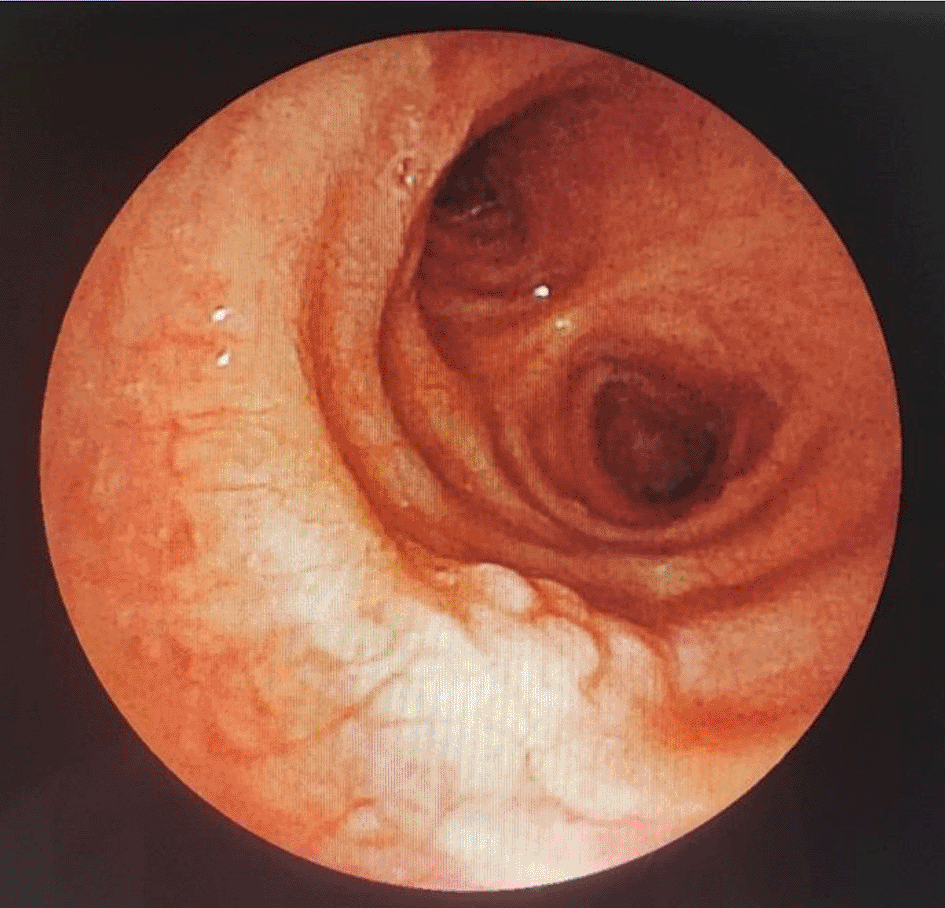

A 43-year-old nonsmoker man was referred to our department for respiratory preparation before surgical excision of an endobronchial HC. Medical history included sinonasal polyposis and diffuse bronchiectasis diagnosed at the age of 12 years with a negative etiological assessment and right lower lobectomy 4 years ago. On admission, the patient had purulent sputum with no other associated symptoms, including fever, dyspnea, or hemoptysis. Chest auscultation revealed wheezing, and the patient’s oxygen saturation level was 93% (room air). The patient was treated for a bronchial superinfection. Results of microbiological investigations were negative. Flexible bronchoscopy performed after the patient improved revealed a yellowish polylobed budding formation that completely obstructed the middle lobe bronchus (Figure 7). Chest CT-scan revealed an endobronchial lesion of fatty density in the middle lobe bronchus measuring 13 mm, responsible for minimal bronchiectasis of the middle lobe downstream, with almost total atelectasis of the latter, minimal bronchiectasis of the superior lingular segment, and sequelae of right lower lobectomy (Figure 8). After a multidisciplinary discussion and consideration of the patient’s history, endoscopic treatment was decided. Rigid bronchoscopy revealed a smooth pale pink tumor that completely occluded the middle lobe bronchus and protruded into the bronchus intermedius (Figure 9). Diode laser treatment (20 W, 620 J) was performed before mechanical ablation of the tumor using the tip of the bronchoscope. No additional instruments were required. After removal, total recanalization of the middle lobe bronchus and its subsegments without endobronchial secretions was observed. Macroscopic examination revealed 2 fragments measuring 1.5 * 1.5 cm and 0.5 cm long axis, yellowish in color and with a smooth surface (Figure 10). No complications such as bleeding, respiratory failure, or superinfection occurred. Histopathological examination of the samples stained with Hematoxylin and Eosin (H&E) showed the presence of nodules of hyaline cartilage admixed with fibrous adipose tissue, spindle cells, and myxoid stroma (Figure 11). The diagnosis of endobronchial HC was confirmed. Flexible bronchoscopy performed 2 months after patient discharge revealed recurrence of a small yellowish formation, which reduced the lumen by 50% and was completely resected with biopsy forceps. Histological examination revealed an ulcerated bronchial mucosa seat of a hyperplastic fleshy bud, without signs of specificity or malignancy. No recurrence was observed after a follow-up period of 12 months.